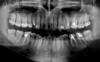

st_ Опубликовано 12 марта, 2008 Автор Поделиться Опубликовано 12 марта, 2008 (изменено) сделал панорамный снимок (орто...) зеркально-отраженный, как я понимаю.кариеса 5 зубов насчиталимежду верхней левой 5кой и 6кой мешок, где скапливается пища, предлагают, как вариант, ликвидировать+ сделать сдвоенную коронку на них, чтобы пища между них не просачивалась.под правой нижней 6ркой маленькая черная область - подозрение на начало кисты...ну и, само собой, прав верх 4рка с одной оставшейся задней стенкой.. Вообще мысли такие - зубы гниют снизу, пища забивается между них и под десну. ну поставлю я коронки, а под ними то тоже запросто может пойти процесс или как? Изменено 12 марта, 2008 пользователем st_ Ссылка на комментарий

pit Опубликовано 12 марта, 2008 Поделиться Опубликовано 12 марта, 2008 сделал панорамный снимок (орто...) зеркально-отраженный, как я понимаю.кариеса 5 зубов насчиталимежду верхней левой 5кой и 6кой мешок, где скапливается пища, предлагают, как вариант, ликвидировать+ сделать сдвоенную коронку на них, чтобы пища между них не просачивалась.под правой нижней 6ркой маленькая черная область - подозрение на начало кисты...ну и, само собой, прав верх 4рка с одной оставшейся задней стенкой.. Вообще мысли такие - зубы гниют снизу, пища забивается между них и под десну. ну поставлю я коронки, а под ними то тоже запросто может пойти процесс или как?Что касается левых верхних 5 и 6 зубов, на мой взгляд, сдвоенные коронки не решат проблемы. Судя по Вашему описанию и представленному снимку - это локализованный пародонтит. Причина - дефекты пломб и направление роста зубов. Сдвоенные коронки будут ухудшать гигиену этой области. Кстати, может мне кажется, в проекции альвеолярной бухты левой верхнечелюстной пазухи затенение округлой формы? Ссылка на комментарий